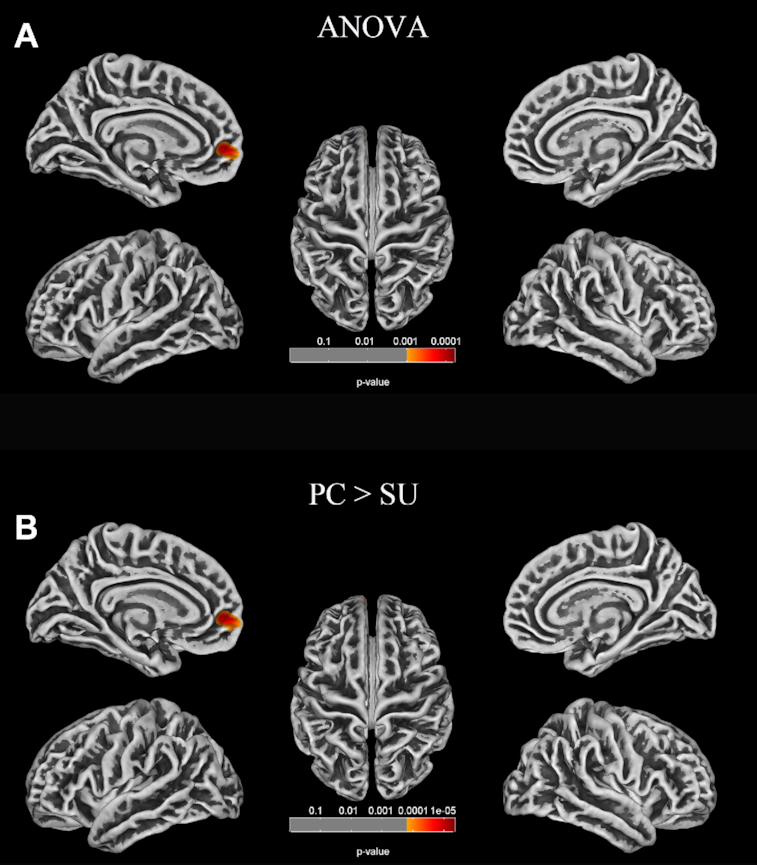

Methods: Here, 3D T1-weighted MR images of brain from 39 healthy controls, 40 depressed patients without suicidality (patient controls), and 39 with suicidality (suicidal groups) were analyzed based on SBM to estimate the fractal dimension, gyrification index, sulcal depth, and cortical thickness using the Computational Anatomy Toolbox. Correlation analyses were performed between clinical data and cortical surface measurements from patients.

Results: Surface-based morphometry showed decreased sulcal depth in the parietal, frontal, limbic, occipital and temporal regions and decreased fractal dimension in the frontal regions in depressed patients with suicidality compared to both healthy and patient controls. Additionally, in patients with depression, the sulcal depth of the left caudal anterior cingulate cortex was negatively correlated with Hamilton Depression Rating Scale scores.

Conclusions: Depressed patients with suicidality had abnormal cortical morphology in some brain regions within the default mode network, frontolimbic circuitry and temporal regions. These structural deficits may be associated with the dysfunction of emotional processing and impulsivity control. This study provides insights into the underlying neurobiology of the suicidal brain.